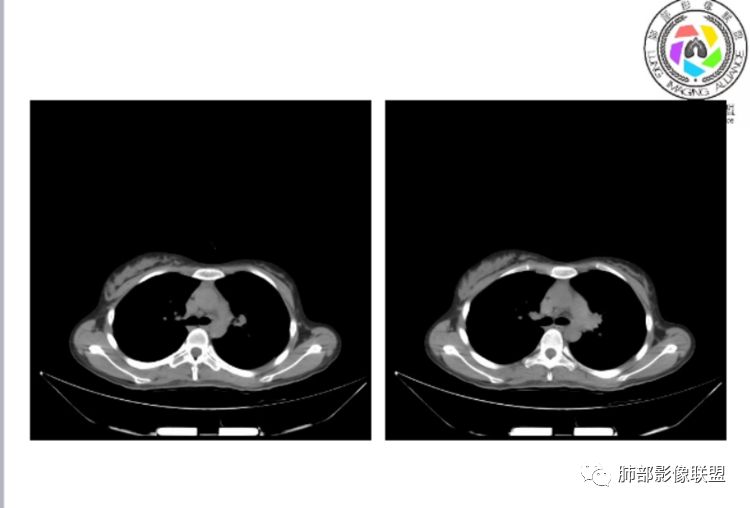

小微:右肺下叶斑片状密度增高影,抗炎治疗6天后复查,双肺下叶出现斑片状密度增高影,排除炎性病变,D2聚体特别高,考虑肺栓塞,肺梗死,建议增强扫描。王开金江津中心医院呼吸科:@岳微-辽宁PLA234医院放射科?支持,患者年轻女性,胸痛主诉,使用雌激素,高危人群,心率快,d二聚体升高,右下叶斑片加肺动脉明显增宽,抗感染无效,要考虑PTE,建议肺动脉ctpa。傅昌瑜:19岁,女性,右侧胸痛2天,发热以中度热为主,D—二聚体升高,肺动脉主干增宽,病灶位于胸膜下,抗感染后增多,近来有服用炔雌醇环丙孕酮片2周期史,诊断:肺栓塞,下一步完善肺CTPA检查。阿仙奴:青年女性,急性起病,胸痛入院,月经不调史,目前服用孕酮片。流感抗体阳性,d二聚体升高,无低氧血症。右肺下叶基底段胸膜下磨玻璃样改变,肺动脉增宽,治疗过程出现发热,复查左下叶胸膜下新发病灶。考虑:肺栓塞(服用孕酮相关)?奔跑的37°Doctor(陆喜红 ) :年轻女性,胸痛 急性病程,有服用雌激素避孕药史(是否有血液循环的改变,高凝状态),实验室D二聚体很高(也是提示血液高凝状态) ,第一次CT,右下肺胸膜下斑片状密度增高模糊影,肺动脉形态密度未见明显异常,抗炎后复查,肺动脉干及其分支,感觉增粗了一点,局部形态有点饱满,双下肺胸膜下片状影增多,锁定肺动脉栓塞应该不会错,建议CTA检查飞鹰行动:青年人,女性,右肺下叶斑片状密度增高影,抗炎治疗6天后复查无好转,,双肺下叶出现斑片磨玻璃影,主肺动脉增粗,结合患者服用的药物和D2聚体特别高,考虑肺栓塞,建议CTA。李:口服避孕药,有危险因素,肺动脉较主动脉增宽,D二聚体增高,胸膜下片状影,考虑肺栓塞;@晨义工张帅,医附属潞河医院呼吸?是否痰中带血很关键,不知有没有张帅:患者入院后第七天出现痰中带血风之子:病程中有发热,D—二聚体升高,肺动脉主干增宽,病灶分布于胸膜下,抗感染后增多,结合服药史诊断:肺栓塞,建议CTPA检查。不支持的地方是没有低氧血症,不明白为什么第二次复查ct双侧乳腺不对称,按理乳腺炎多见于哺乳期张帅:大家方向都在考虑肺栓塞:我提问两个问题:1 周围毛玻璃怎么回事?2左下肺小叶间隔增宽怎么回事?笨丫头:周围的磨玻璃应该考虑是肺梗死后出血渗出,同时合并机化性炎症小叶间隔增宽,我考虑应该是梗死后炎性渗出wonderful:我不支持肺栓塞 不能解释发热原因

张帅:好多老师都在说肺动脉增宽。肺动脉增宽标准是多少?程磊:29。或者比同层主动脉比值大于等于1

张帅:我量的虽然不标准,但不到24

2、肺动脉高压(中心肺动脉扩张),有时可见肺动脉区高密度影。